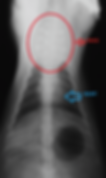

X-ray of a cat with mediastinal lymphoma

X-ray of a cat with lymphoma of the kidney